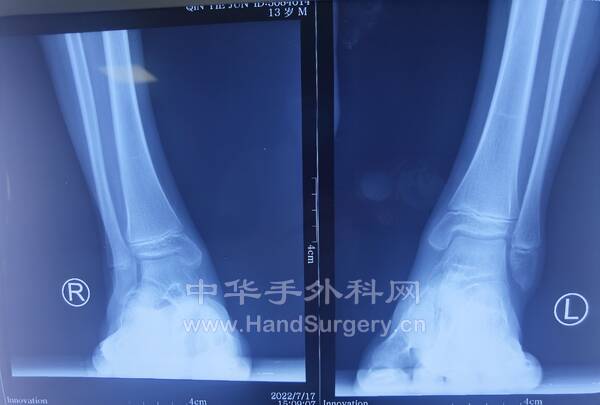

明日需要手术的右足马蹄外翻足,扁平足小患者资料(图18--41)

明日需要手术的右足马蹄外翻足,扁平足小患者资料(图1-24)